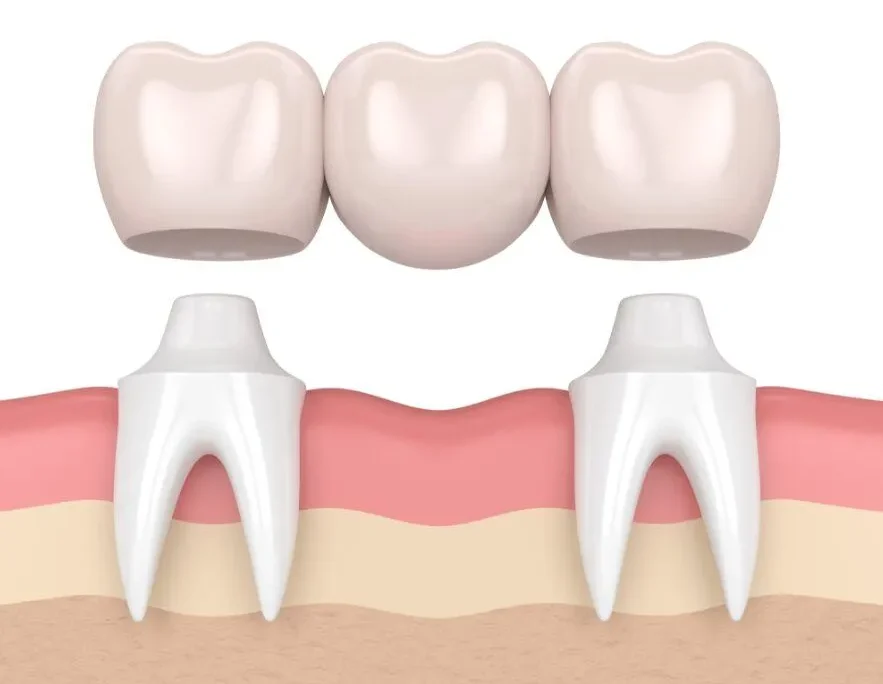

Một chiếc cầu răng tiêu chuẩn thường bao gồm ba phần chính:

- Mão răng (Crowns): Là hai chiếc răng sứ được thiết kế để đặt lên hai chiếc răng thật khỏe mạnh ở hai bên khoảng trống mất răng. Hai chiếc răng này đóng vai trò như trụ cầu, hay còn gọi là trụ đỡ.

- Nhịp cầu (Pontic): Là chiếc răng giả nằm giữa hai mão răng, có nhiệm vụ lấp đầy khoảng trống của chiếc răng đã mất. Chiếc răng này được thiết kế sao cho có hình dáng và màu sắc giống hệt với răng tự nhiên.

Nguyên tắc phục hình của cầu răng là sử dụng các răng thật khỏe mạnh lân cận làm điểm tựa để nâng đỡ và giữ chắc chiếc răng giả ở vị trí bị khuyết. Để làm được điều này, nha sĩ sẽ mài nhỏ hai chiếc răng trụ để làm cùi răng, sau đó gắn mão răng và nhịp cầu lên trên.